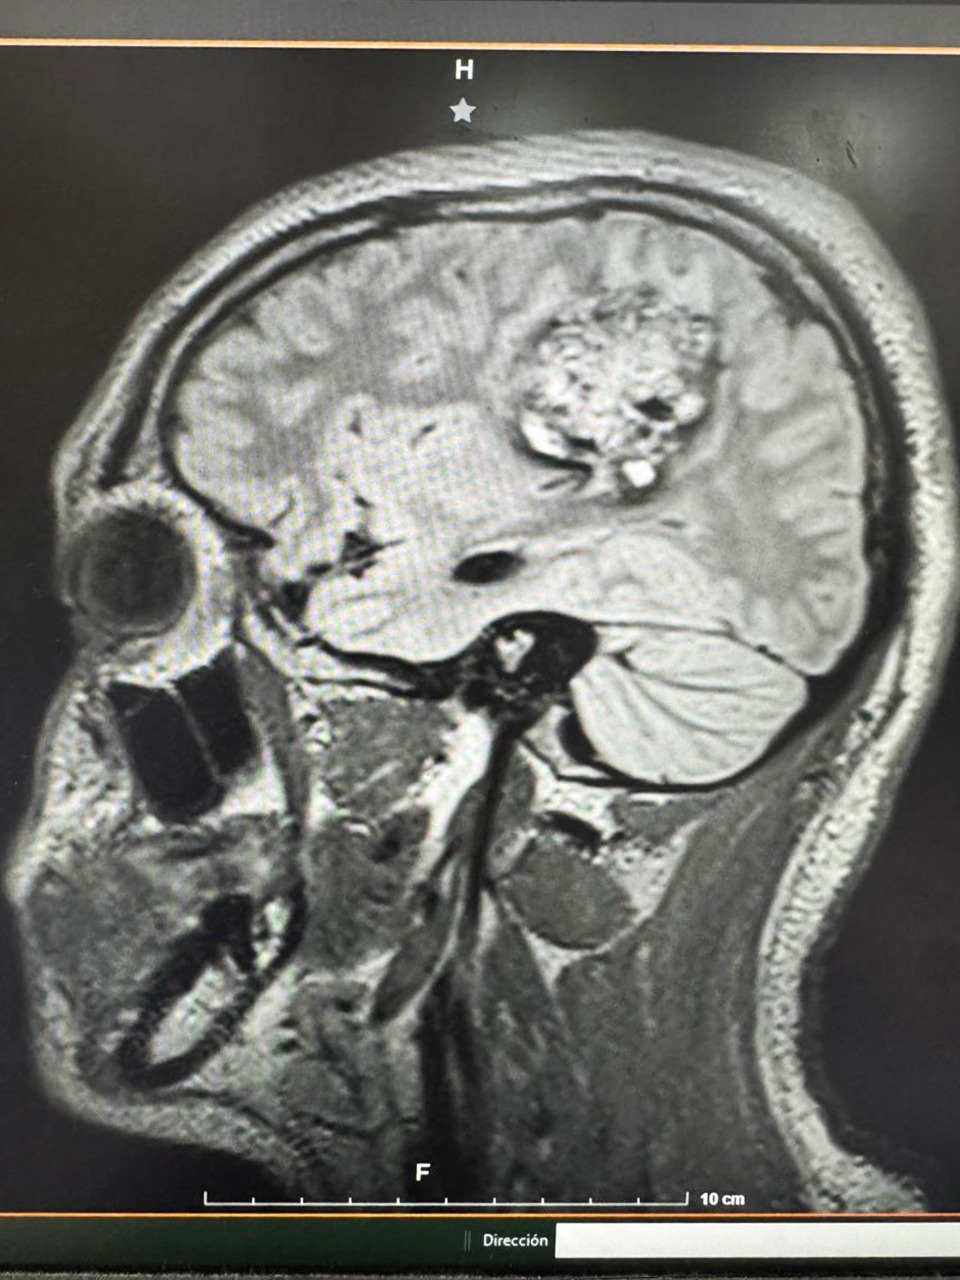

Especialistas de la Unidad Médica de Alta Especialidad (UMAE) del IMSS en Yucatán realizaron con éxito la primera craneotomía en un paciente pediátrico de 16 años que permaneció despierto durante la operación, lo que permitió monitorear en tiempo real sus funciones del habla, cognitivas y motrices mientras le extirpaban un tumor cerebral de cinco centímetros.

El procedimiento, encabezado por el neurocirujano pediatra doctor Gabriel Cachón Cámara, se llevó a cabo tras detectar un cavernoma, una lesión vascular compleja ubicada en una zona crítica del cerebro relacionada con el lenguaje y el movimiento. El joven Francisco, originario de Cancún, Quintana Roo, llegó a la UMAE después de sufrir crisis convulsivas, pérdida del conocimiento y dificultades para hablar y moverse.

Durante la cirugía, el equipo de anestesiólogos aplicó la técnica “despierto-dormido-despierto”, que permitió mantener al paciente consciente en etapas clave de la intervención. Con apoyo de un sistema de navegación cerebral tipo GPS, los especialistas pudieron localizar el tumor con precisión y retirarlo totalmente, preservando las funciones motoras y del lenguaje del adolescente.